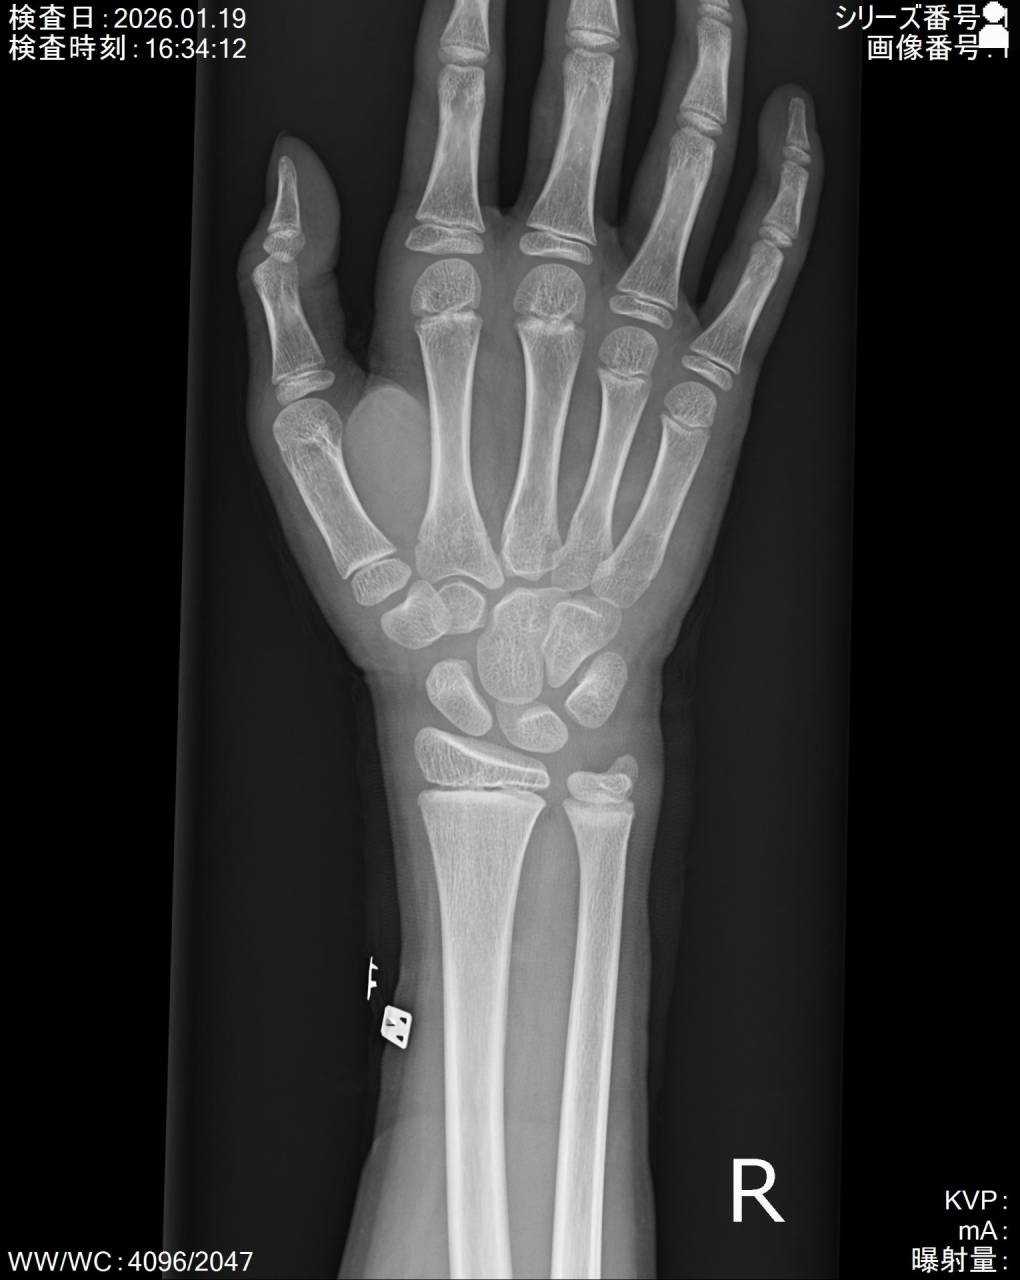

撮影した画像を確認すると舟状骨近位部に骨折がありました。

この部位は血管の走行から癒合しづらい部位でもあるので慎重に進めていかなければいけません。

癒合しづらい要因として血管の走行があります。

骨を修復するのに重要な栄養血管の血流が悪い部位なので、偽関節や無腐性壊死を引き起こす恐れがあるので注意が必要です。